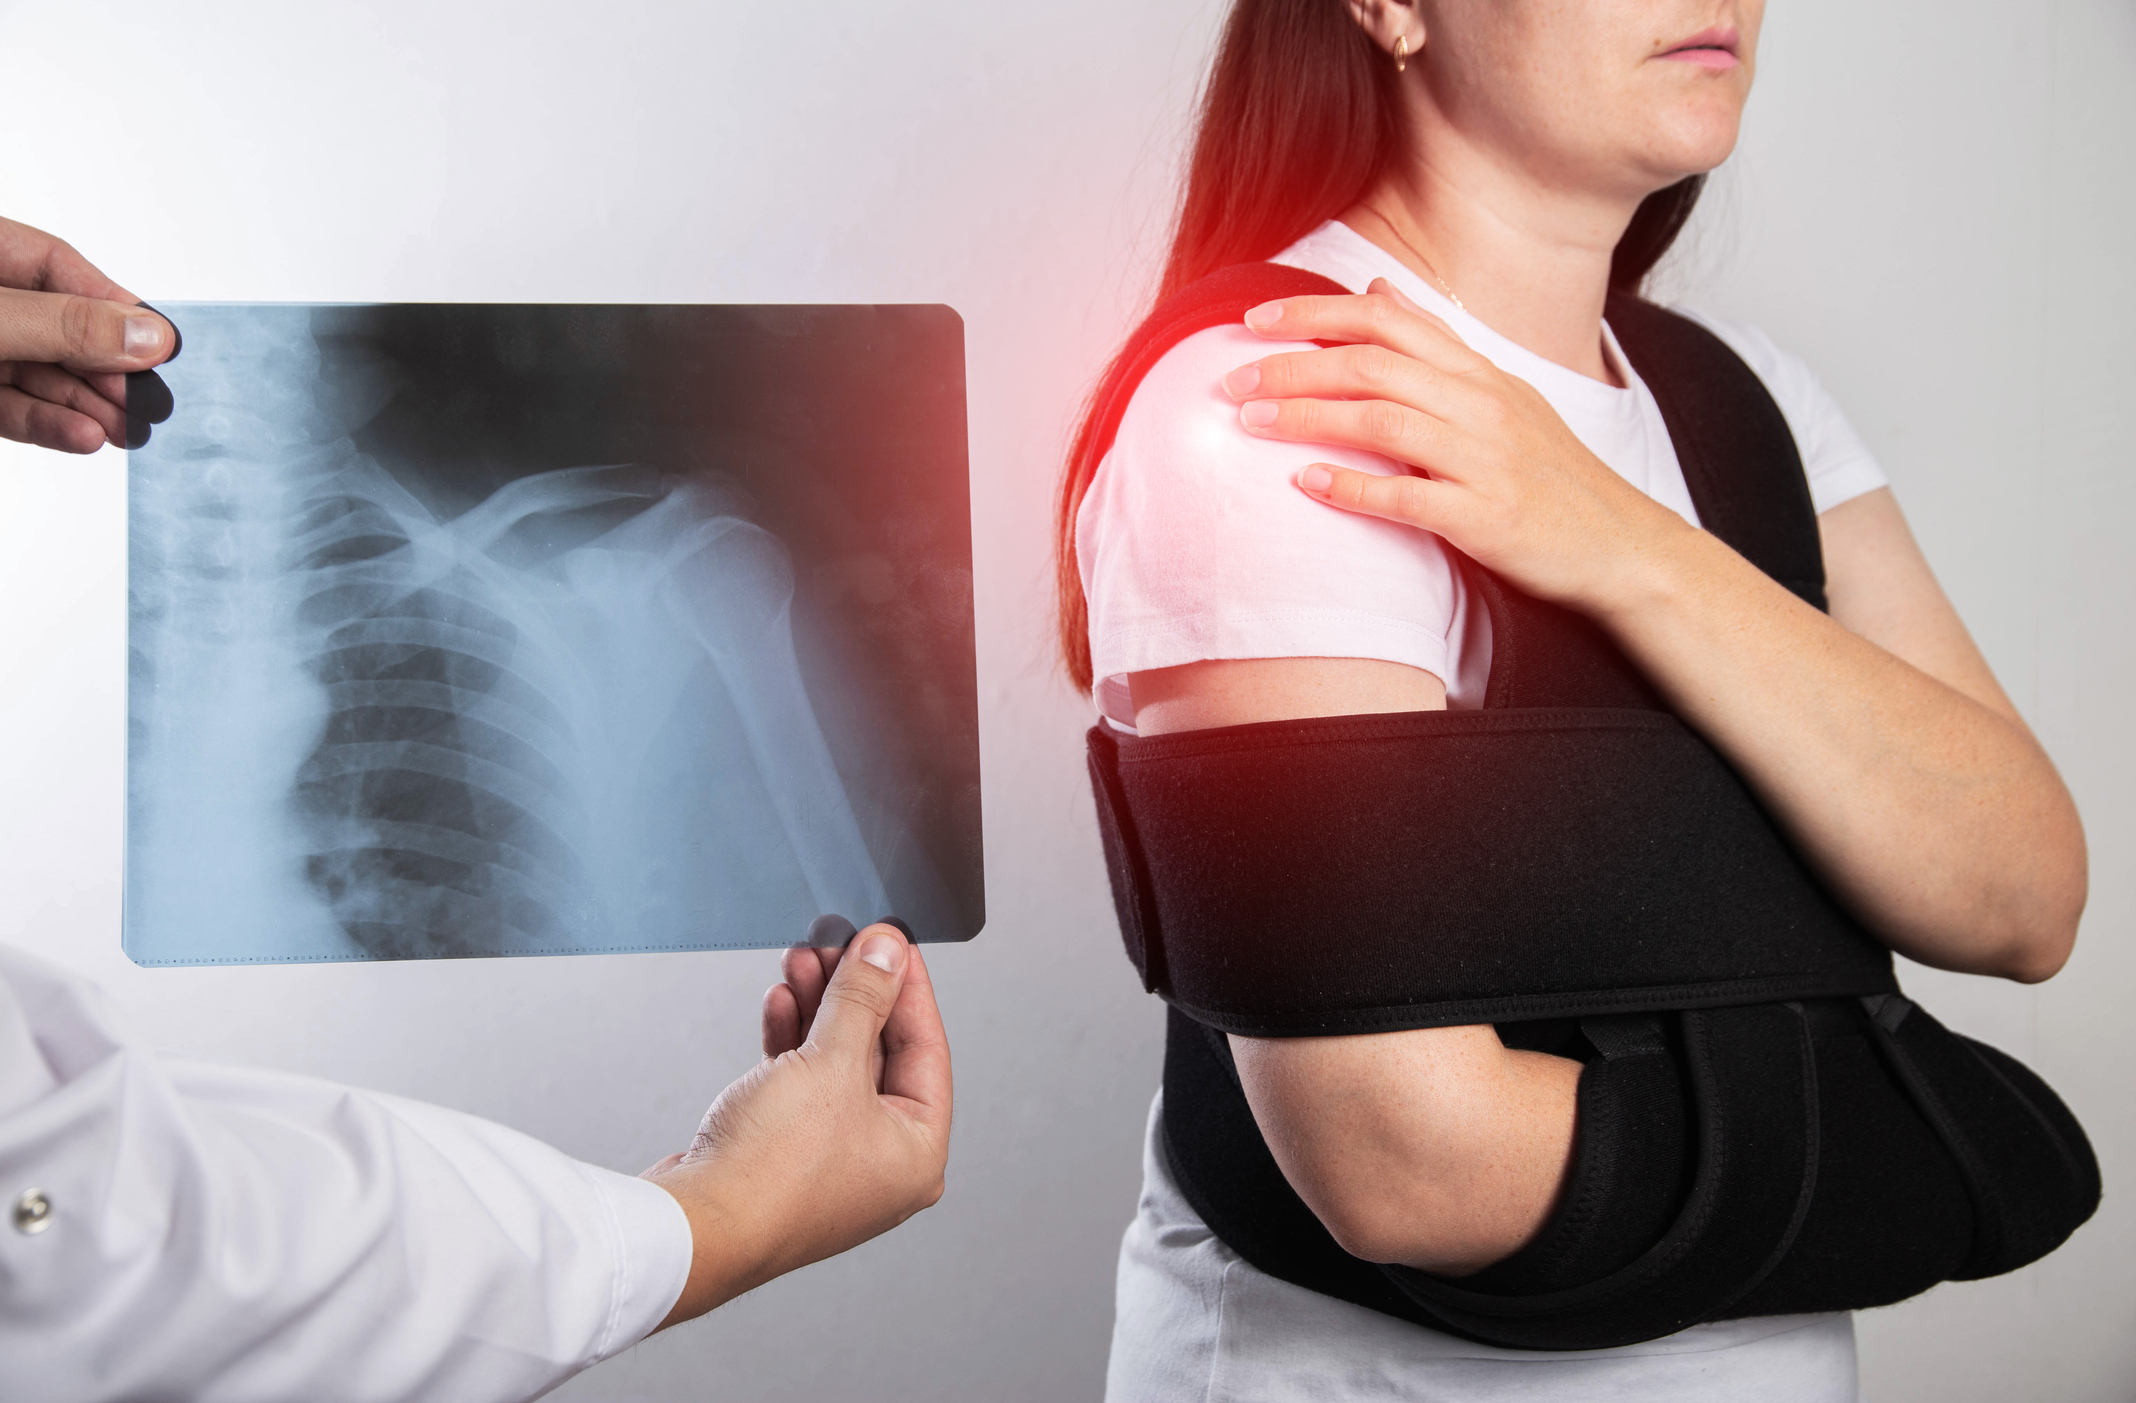

Nadlahtnica je edina kost v zgornjem delu roke. Ker je tako močna, jo običajno zlomi šele močna sila poškodbe, kot je hud padec ali prometna nesreča.

Odvisno od vrste zloma (in morebitnih drugih poškodb, ki ste jih utrpeli) boste za okrevanje po zlomu nadlahtnice verjetno potrebovali nekaj mesecev.

Zlome nadlahtnice delimo v grobem na 3 skupine – zlom zgornjega, srednjega ali spodnjega dela. Kakšno zdravljenje bo primerno je v veliki meri odvisno od lokacije zloma.

Zlomi zgornjega dela nadlahtnice (proksimalni zlom)

Večino zlomov proksimalnega dela nadlahtnice je mogoče zdraviti brez operacije, če kostni fragmenti niso pretirano premaknjeni. Če so prisotni veliki premiki se pogosto opravi operacija, da se omogoči optimalno okolje za celjenje kosti.

Približno 80 % zlomov proksimalne nadlahtnice se uspešno zdravi brez kirurškega posega, zlasti pri starejših osebah in otrocih. Pri konservativnem zdravljenju je potrebno imobilizirati zgornji ud ob telo za obdobje 2-3 tednov.